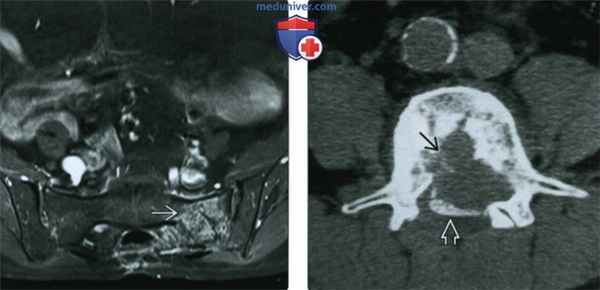

(Слева) МРТ, аксиальная проекция, режим Т1 с подавлением сигнала от жира, с контрастным усилением: через год после краевой резекции (потребовалась для сохранения функции) визуализируется рецидив опухоли в левом крыле крестца. Хордома является локально агрессивной опухолью, которая характеризуется высоким уровнем рецидивов, особенно при краевой резекции. Со временем часто появляются метастазы.

(Справа) КТ,аксиальная проекция с миелографией: хордома тела поясничного позвонка, распространяющаяся на эпидуральное пространство и сдавливающая дуральный мешок.